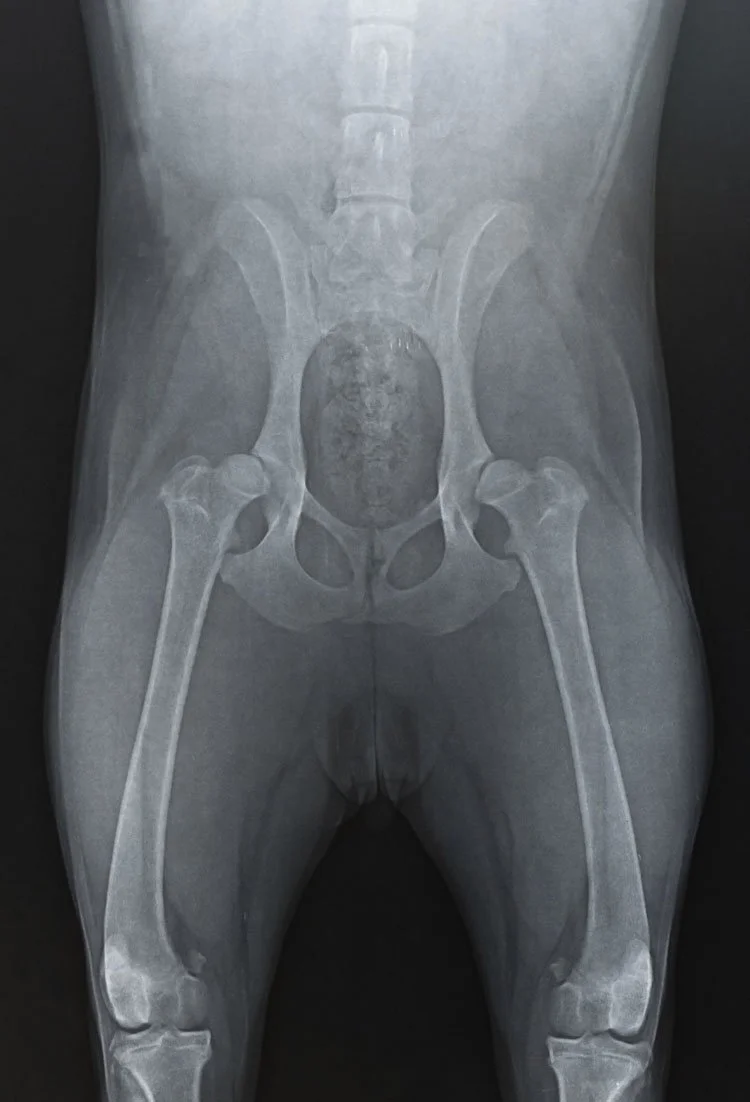

1. Canine Hip Dysplasia

Canine hip dysplasia begins to affect dogs as they age. If your dog has the disease, its hip joints will loosen and become unstable. This condition can be exacerbated by age and weight gain. Affected dogs will lose cartilage over time and begin to develop bone spurs in their hip joints. Canine hip dysplasia occurs most frequently in large breed dogs. At Groodle Doodle Ranch, all of our dogs have hip radiographs and only those with excellent or good scores move onto becoming parent dogs.